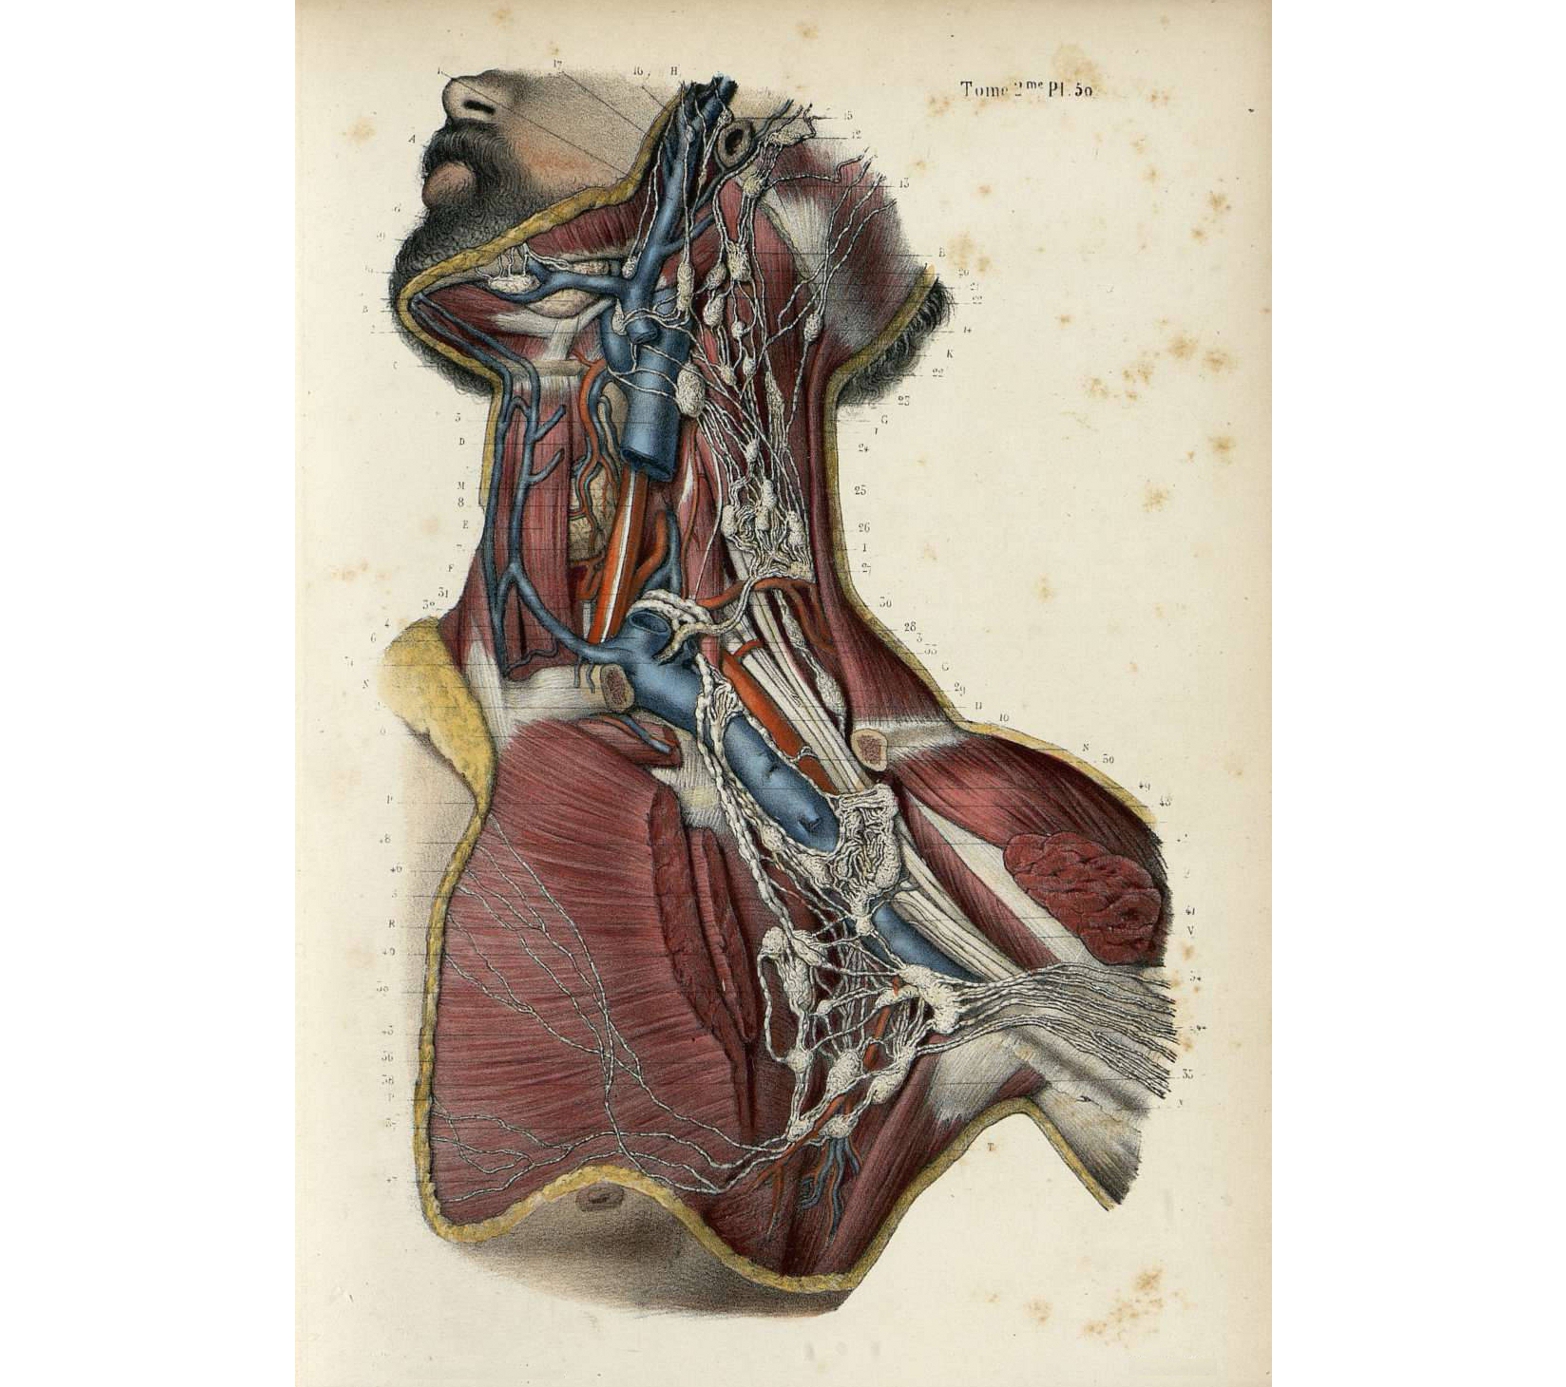

El passat 31 de desembre de 2014 es complien cinc cents anys del naixement d’Andreas Vesal (nascut a Brussel·les amb el nom d’Andries van Wesel), artista i anatomista renaixentista que segons molts autors representà una autèntica revolució de l’anatomia.

Aquesta exposició vol aprofitar l’efemèride per revisar aquests cinc segles d’anatomia des de les tres vessants que representa Vesal: la del mestre, la del científic i la de l’artista.